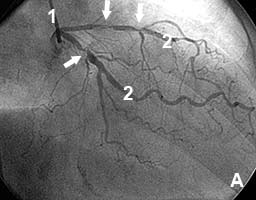

Пациент с жалобами на боли в сердце в покое (нестабильная стенокардия). В анамнезе - инфаркт миокарда.

На коронарограмме (рис 6а) - множественные стенозы ветвей левой коронарной артерии.

В место стенозов установлены коронарные стенты. Стенозы полностью устранены (рис.6б)..

Сразу же после вмешательства приступы болей прекратились.

Рис.6 Множественные стенозы ветвей левой коронарной артерии до (А) и после (Б) стентирования.

1 - катетер; 2 - контрастированные артериальные ветви; стрелками отмечены зоны стенозов. |